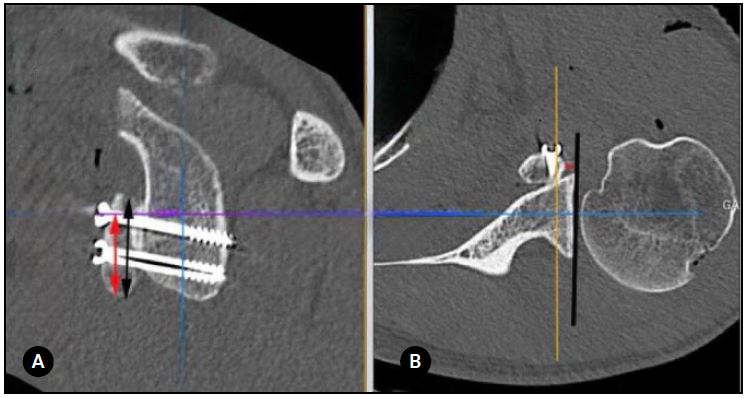

Se mostraron simultáneamente en la misma pantalla las imágenes en 2 planos (sagital y axial). Luego se realizaron las siguientes 4 medidas para cada paciente: (A) la posición del injerto coracoideo en el plano sagital, (B) la posición del injerto en el plano axial, (C) la dirección de los tornillos (ángulo), y (D) el ángulo de contacto (Figs. 1 y 2).

En el plano axial, el injerto coracoideo se consideró “al ras” cuando el borde lateral del injerto estaba entre 1 mm lateral y 4 mm medial a la línea articular; “medial” cuando estaba >4 mm medial a la línea articular; y “prominente” cuando era >1 mm lateral a la línea articular. El ángulo α se definió como el ángulo entre el eje del tornillo y el hueso subcondral glenoideo. Finalmente, el ángulo de contacto fue el ángulo formado entre la superficie posterior del injerto coracoideo (medido entre los 2 tornillos) y el cuello anterior de la glena. Se consideró contacto completo si el ángulo era ≤4 e incompleto cuando era >4. Si el espacio entre el injerto y la glenoides era >1 mm, asumimos que no existía contacto.16

Figura 2. A) Cálculo de la dirección del tornillo (ángulo). El punto rojo indica el ángulo formado por el eje del tornillo y el hueso subcondral glenoideo (líneas verdes). B) Evaluación del contacto del injerto coracoideo con la superficie glenoidea anterior. El ángulo de contacto se define desde la superficie posterior del injerto coracoideo (línea verde entre los puntos rojo y azul) y el cuello anterior de la cavidad glenoidea (línea verde entre los 2 puntos azules).